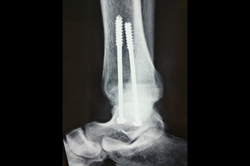

Ankle